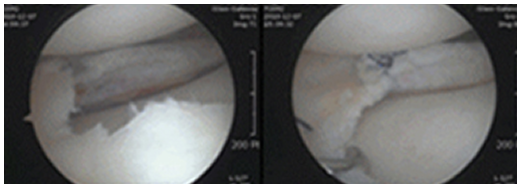

연골판 파열 치료방법

1 ) 봉합술

일반적으로 관절경을 이용하여 반월연골판을 봉합합니다. 봉합하는 방법에는 여러 가지가 있습니다.

첫 번째 방법은, 관절경 시야에서 파열된 부위를 확인한 후 봉합 기구를 이용하여 관절 내부에서 시작해

관절 외부로 실을 뽑아내어 관절막에 매듭을 만드는 방식입니다. 두 번째 방법은, 관절 외부에서 유도관을 이용하여

파열 부위 및 반월연골판을 통과시킨 후 봉합사를 관절 외부로 빼내어 관절막에 매듭을 만드는 방식입니다.

바른마디병원 반월연골판 봉합술은 파열의 위치와 크기에 따라 적절한 방법을 선택합니다

2 ) 절제술

봉합술이 어려운 경우나 증상이 심한 반월연골판 파열이 있는 경우,

관절경을 이용하여 손상된 반월연골판을 절제하는 수술을 시행합니다.